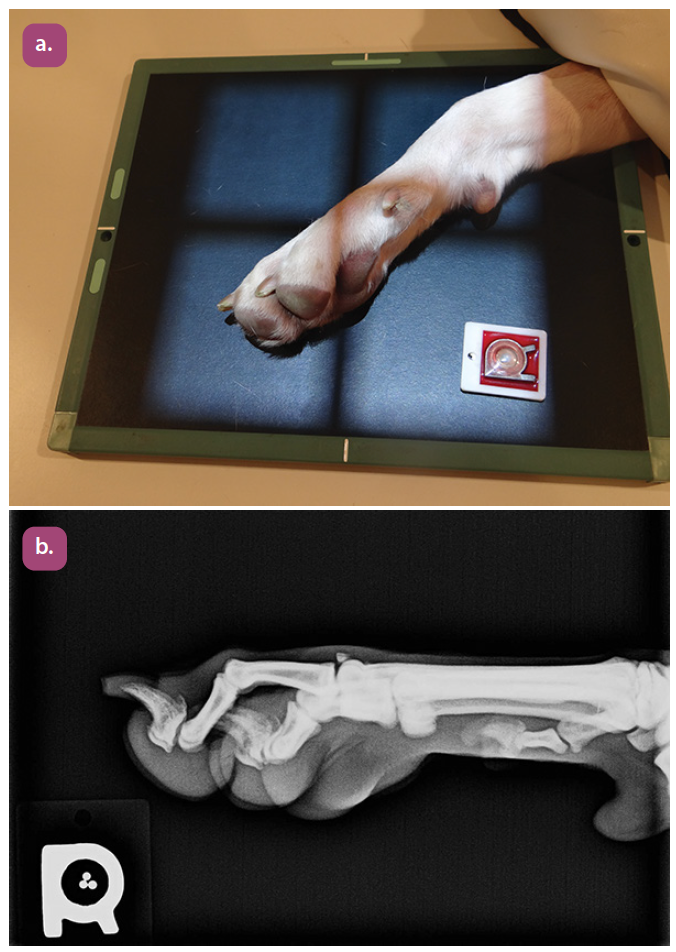

lateral projection of the digits

mediolateral projection of the phalanges